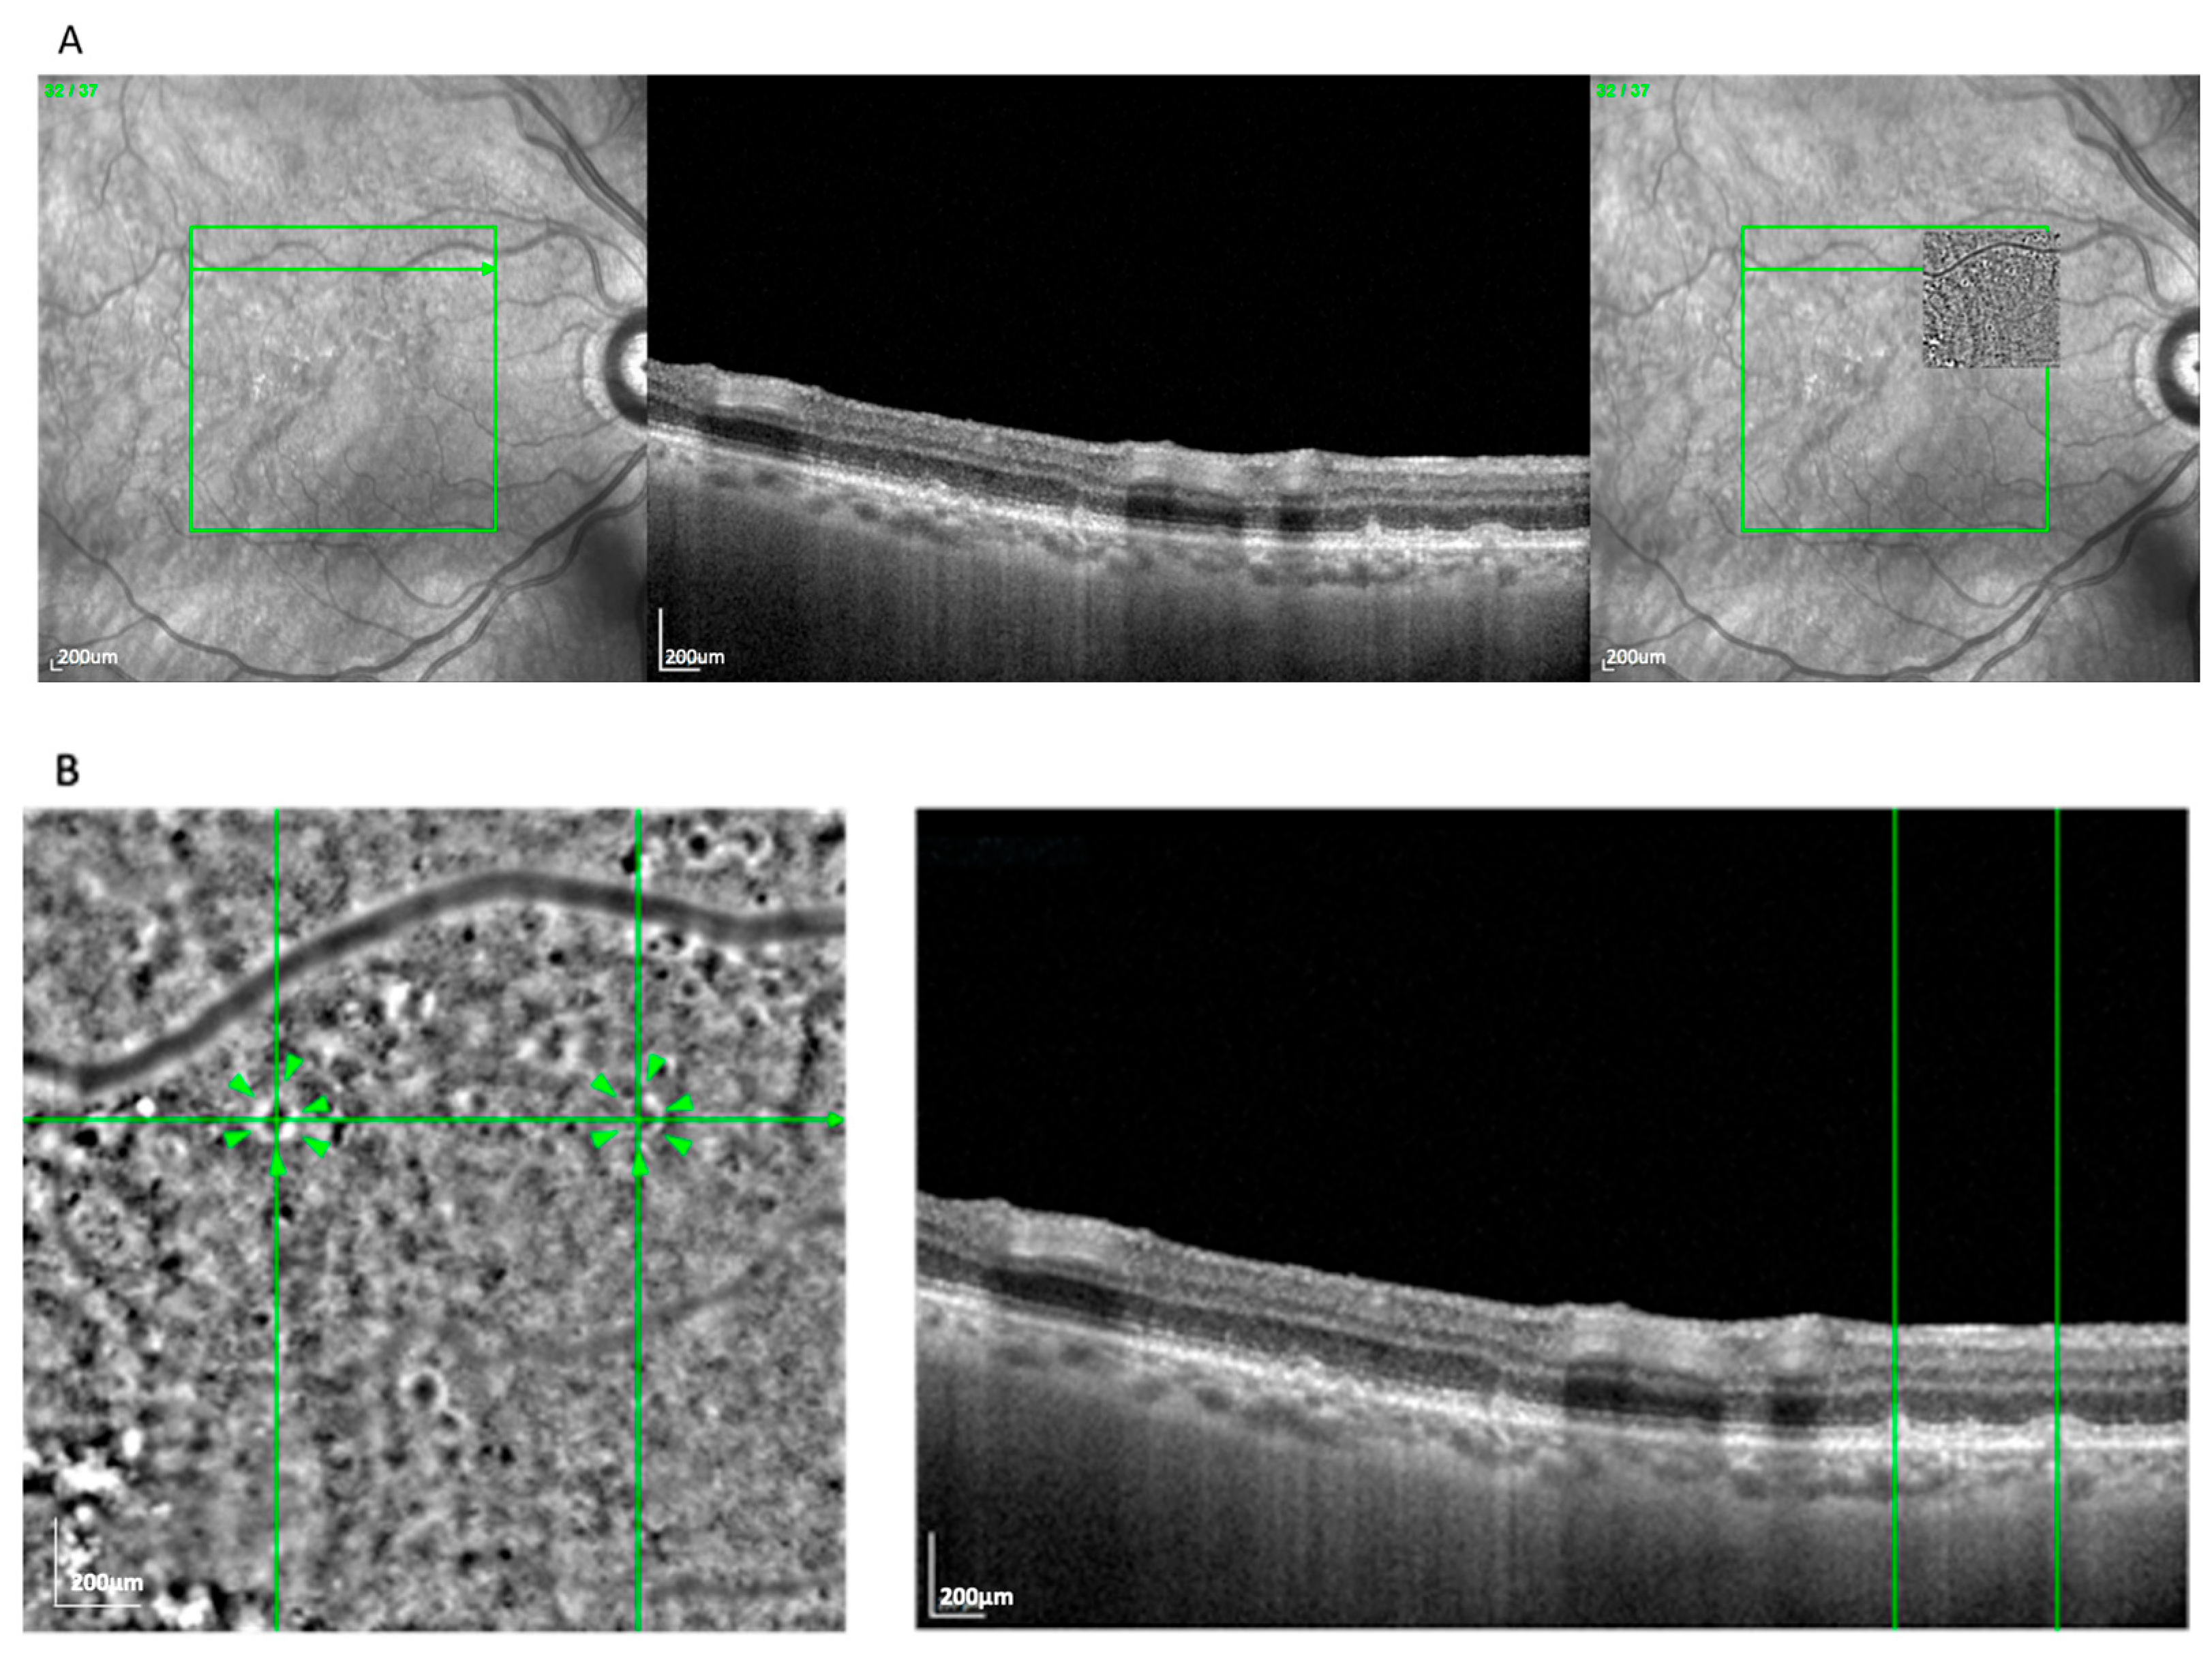

The clump pattern (Figure 3) was seen in 31 eyes (25.8%) and featured a mosaic of similarly sized (~230 μm), well-organized hyperreflective clusters beneath the presumed RPE layer. This pattern corresponded with soft drusen, based on size, location, and en face OCT correlation. The overlying RPE signal was often elevated or irregular, consistent with drusen-induced displacement [17]. Clumps were most commonly observed in nvAMD cases (74.2%) compared to GA (25.8%).

Figure 3.

(A) Correlation of a clump lesion visible on an AO-TFI image in RPE mode with the OCT finding using vessel structure for orientation. (B) Visualization of clumps and high-magnification view of the correlated soft drusen. Green lines highlight corresponding on between en face and cross-sectional view. Arrowheads show the Pattern Clump.